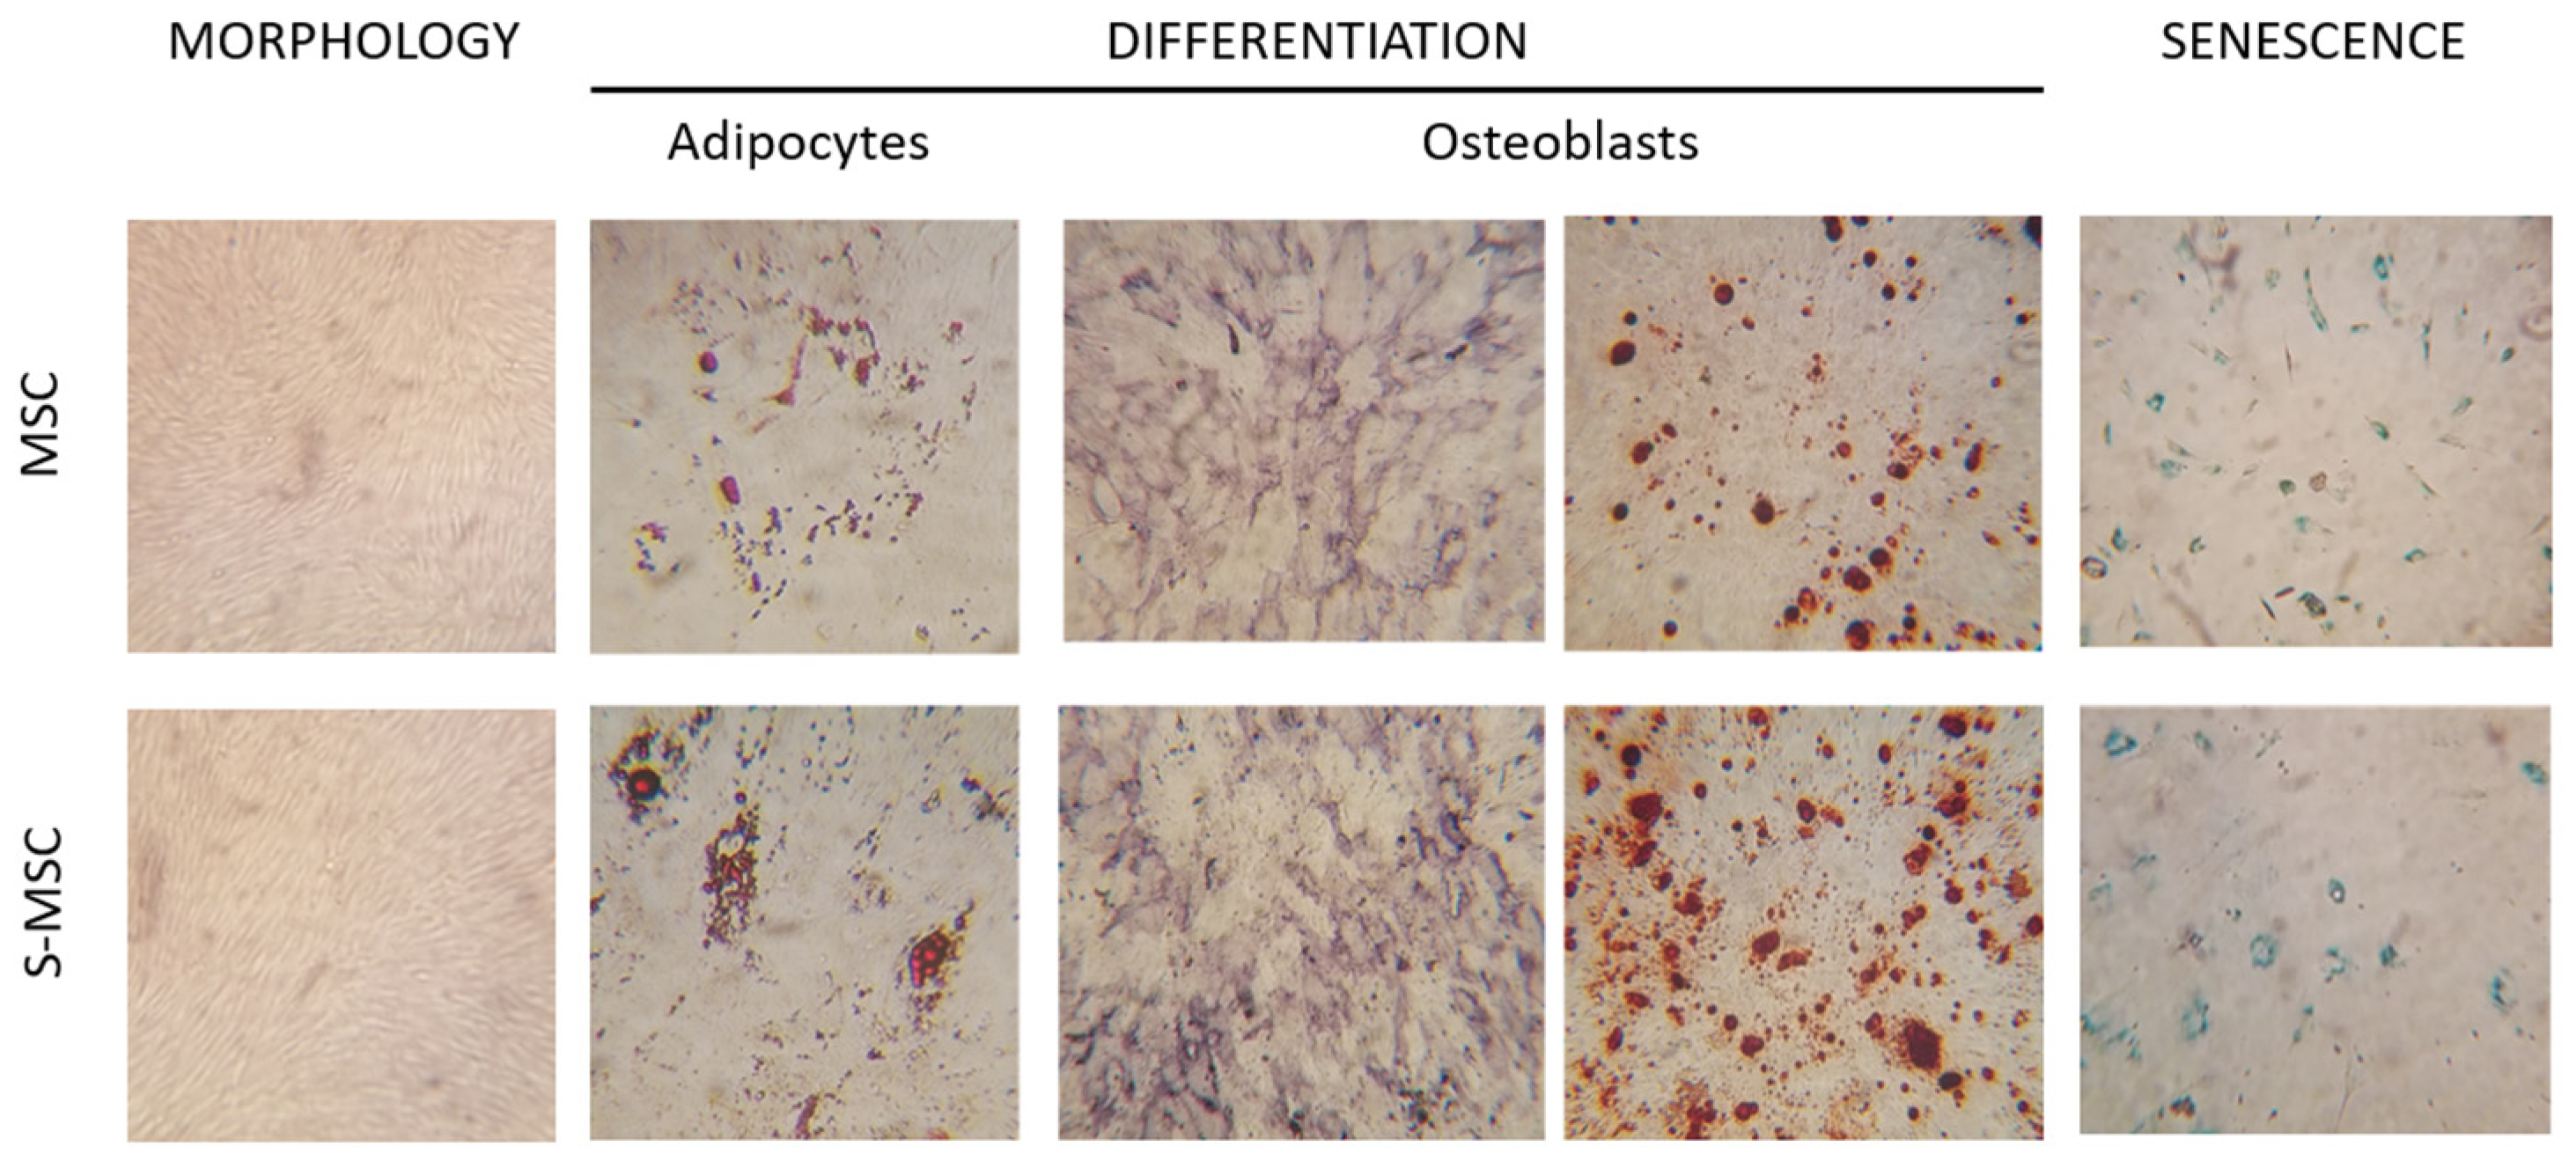

2.2.2. Differentiation Assay

2.2.3. Senescence

3.1. MSC and S-MSC Characterization